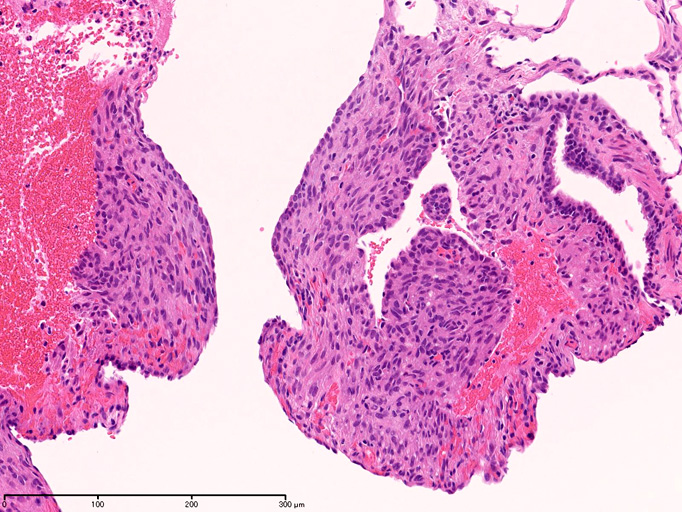

LAMの肺病変

嚢胞周囲または肺血管, リンパ管, 細気管支にそうLAM cellの浸潤, 集簇を特徴とする。LAM cellには2種類が認められ, 小型紡錘形細胞と細胞質の豊富な類上皮様細胞があり, 紡錘型は主に集簇巣の中心に存在し増殖能が高い。 類上皮様LAM cellは辺縁部に多く, 増殖能は低いがHMB45を強く発現している。

LAM cellの免疫染色--SMA, desmin, vimentin(vimentinはいつも陽性とはならない)が陽性となりmuscle lineageであるが典型的な筋細胞と異なり,

嚢胞形成はLAM cellの増殖と関連しており, 細胞が産生するmatrix metalloproteinases(MMPs)による組織破壊によるらしい。

免疫染色